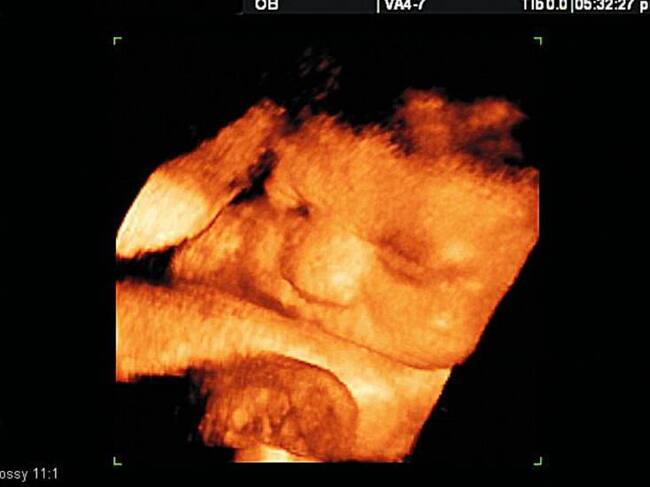

Foto Colprensa